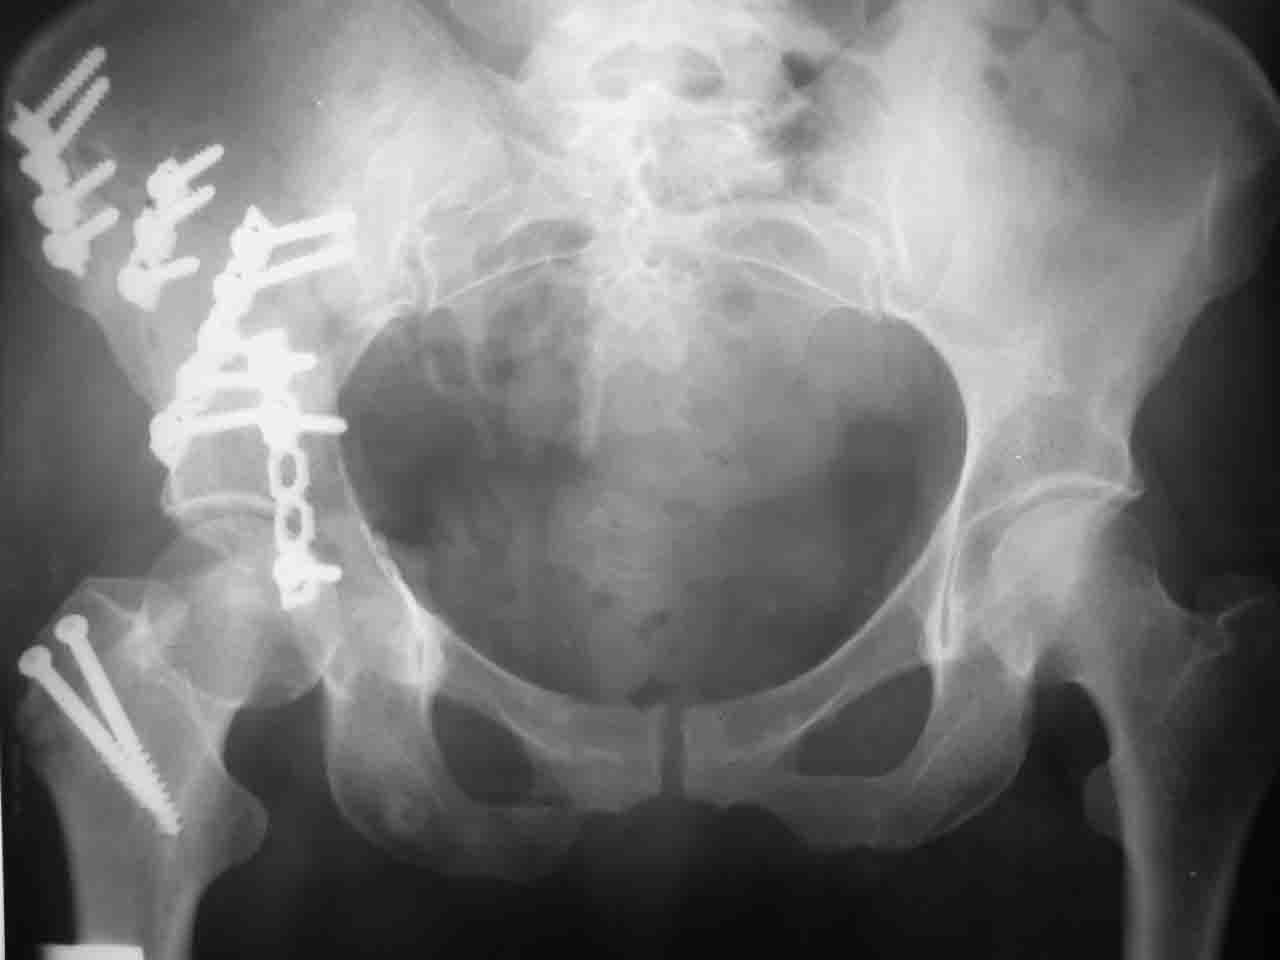

Сложностью, ассоциативностью характера перелома, я бы с радостью воспользовался мининвазивной перкутанной фиксацией винтами, но боюсь, что результат был бы ещё хуже, техникой непрямой репозиции перелома не владею, поэтому пытаясь получить анатомичную впадину приходится широко открывать, по крайней мере пока, а дальше буду пытаться уменьшать пространство...

Илеофеморальный доступ не совсем передний и сравнительно с илеоингвинальным, и Кохера-Лангенбека открывает весь наружный таз кроме самых передних отделов лонных костей, фиксацию которых я не ставил в задачу. Обширность диссекции, большая длительность операции и более высокий риск гетерооссификации - отрицательные моменты в обмен на возможность легче ориентироваться.

Комбинированные доступы - хорошая альтернатива, меньший процент осложнений, но я заметил , что без сбора *мозаики* безымянной кости сложно отрепонировать переднюю колонну, а с нерепонированной передней колонной невозможно анатомично собрать заднюю колонну и соотв. фрагменты стенки - так.что все равно открывать придется широко. Поэтому выбирая комбинированный

подход, передний доступ должен был бы быть продлен до задней трети крыла безымянной кости, а задний - практически до того же уровня, оставляя 6-7 см мостик. При этом вместо одного послеоп. рубца у больного остаются два сравнительно длинных.

Вопрос доступа к вертлужной впадине при остеосинтезе задача не простая. Конечно, у Летурнеля и Тайла всё давно описано, нам остается только брать на вооружение. Но сами понимаете, что не бывает двух одинаковых ситуаций, поэтому в каждом случае вопрос решается сугубо индивидуально. Наша главная цель - восстановить анатомию с нанесением минимальной дополнительной травмы тазобедреннному суставу, думаю с этим никто не поспорит. Расширенный илиофеморальный доступ уж слишком травматичен (как сказал один коллега "таз лежит отдельно, больной отдельно").Стоит ли делать из пациента анатомический препарат для того чтобы легче ориентироваться. Да и нужно ли собирать всю "мозаику"? Мы применяли при таких операциях своеобразную операционную хитрость - сначала устраняли грубое смещение крыла под гребнем с фиксацией так называемой "плавающей" пластиной (временно фиксированной на двух винтах)- доступ или продлевали боковой, или делали небольшой дополнительный разрез над гребнем. Это позволяло устранить грубое смещение и захождение отломков тела повздошной кости, что значительно облегчало репозицию и остеосинтез впадины над сводом. Основное внимание конечно же уделяли нагружаемому задне-верхнему отделу. Сообщите ваш адрес, пришлю схемы и рентгенограммы.